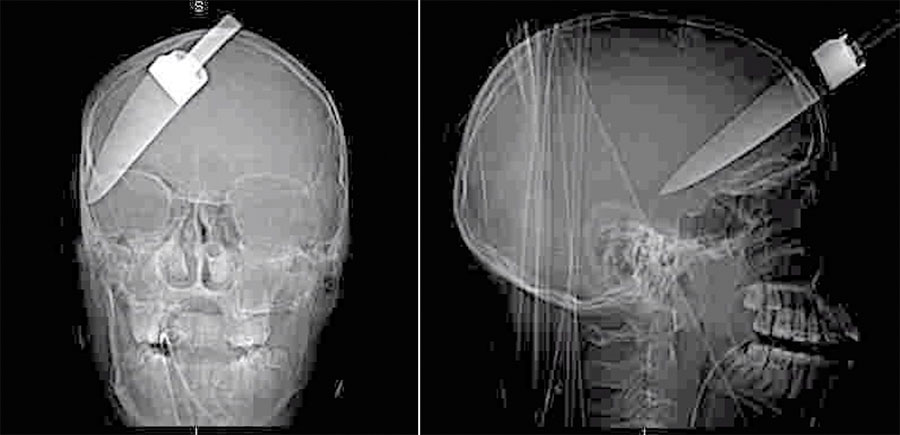

Ahmed, 16 ani, împreuna cu alţi doi prieteni au fost atacaţi de Yassin Elmansouri într-o staţie londoneză de autobuz, la ora 16:40. Yassin Elmansouri încerca să îi fure telefonul mobil unuia din prietenii lui Ahmed. Când au încercat să il oprească, agresorul a scos un cuţit de bucătărie şi i-a înjunghiat pe cei trei tineri: unul a fost înjunghiat în stomac, altul a suferit răni minore la umăr, iar cel de-al trei-lea, Ahmed, a suferit cele mai grave răni, cuţitul rămânându-i blocat în craniul. Mânerul cuţitului s-a rupt atunci când atacatorul a incercat să îl scoată din capul victimei. Ahmed a fost dus de urgenţă la spital, având încă cuţitul încă blocat în cap.

Ahmed a supravieţuit atacului dar va urma un tratament de recuperare pe viaţă, datorită faptului că i-a fost extras 5% din creier.